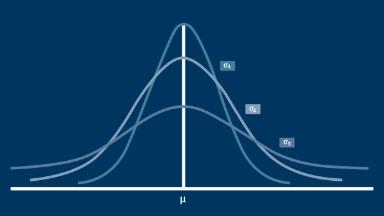

Biostatistics is the body of knowledge that we can use to measure variability and describe the average individual, that is, to describe the central tendency of the population. By statistically comparing these features of two or more groups of individuals, we can help determine the root cause of the effects that we observe.

- describe measures of variability and central tendency